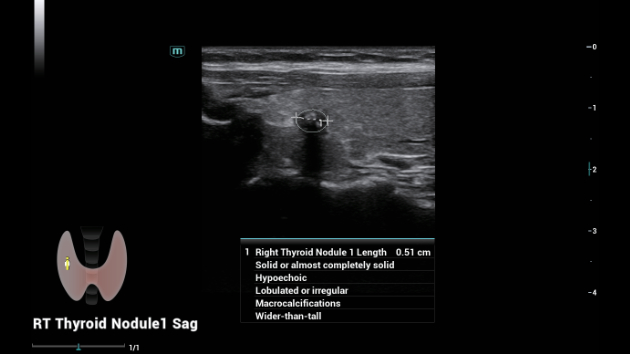

Soluzioni di diagnostica per immagini complete con tecnologia ZST+

La piattaforma ZST+ è un'innovazione straordinaria, che rappresenta un'evoluzione nel campo dell'ecografia. Grazie alla trasformazione delle metriche a ultrasuoni dal beamforming convenzionale all'elaborazione basata sui dati di canale, supera la tradizionale limitazione del trade-off tra risoluzione spaziale, risoluzione temporale e uniformità dei tessuti, offrendo una qualità d'immagine eccezionale per infinite soluzioni di imaging con miglioramenti continui.